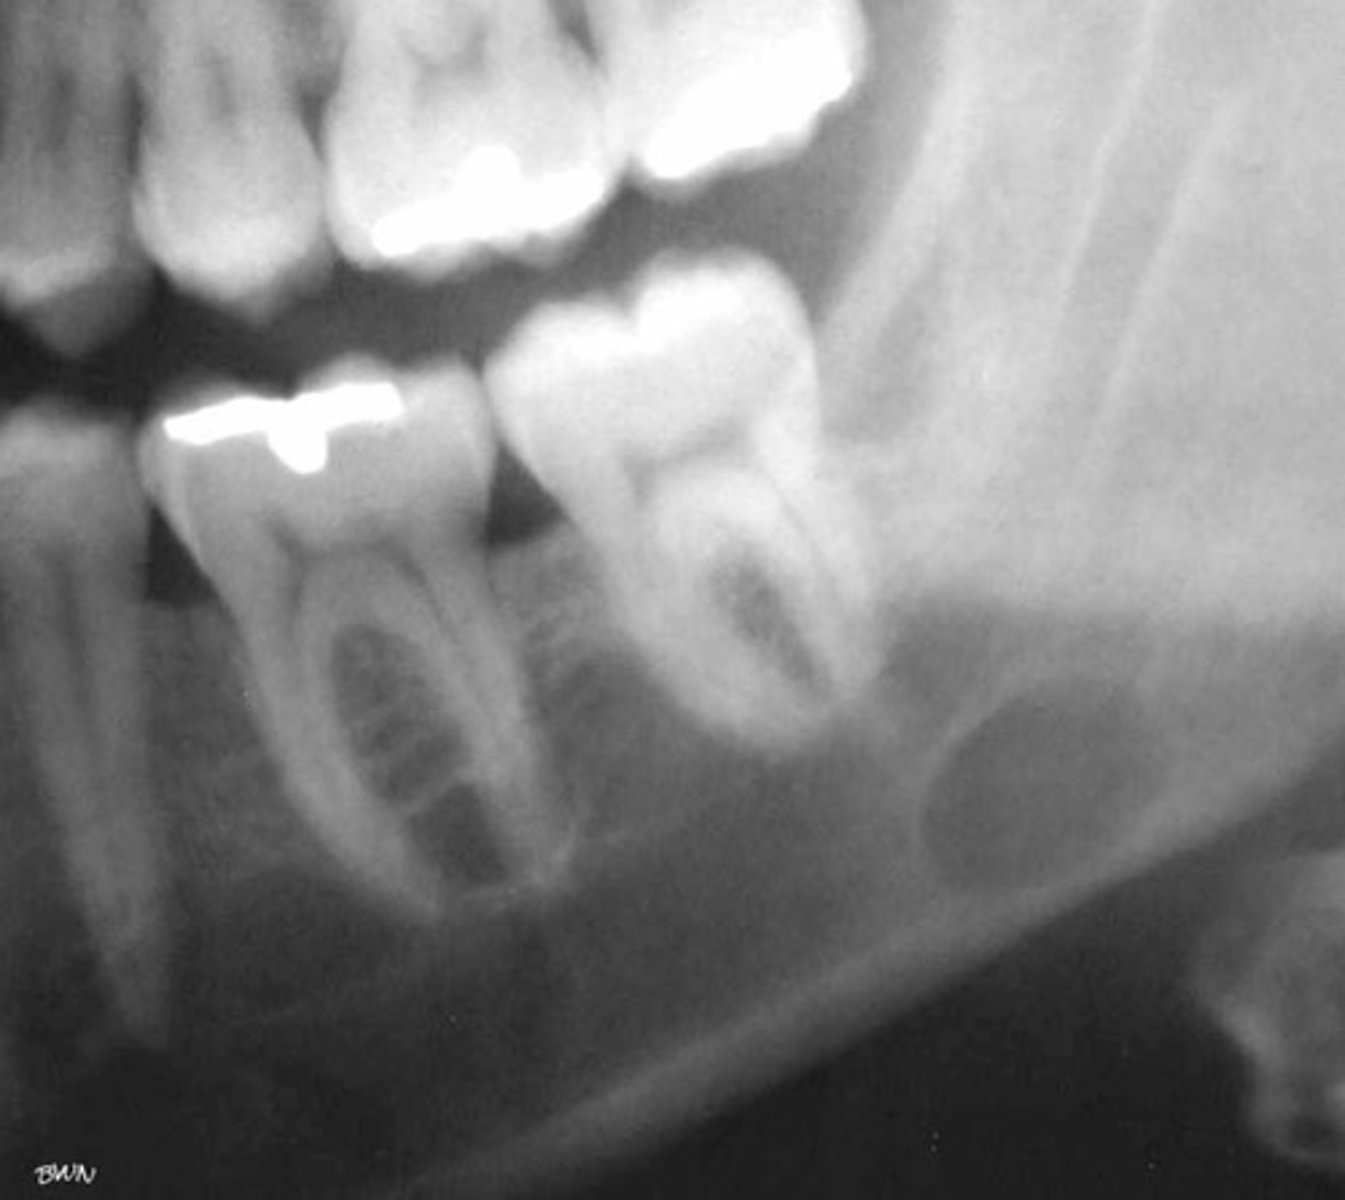

how would you describe the lesion?

A. well-defined, non corticated, periapical radiolucency associated with tooth number 14

B. ill-defined, non corticated, periapical radiolucency associated with tooth number 14

C. well-defined, corticated, pericoronal lesion with radiopaque flecks associated with an impacted tooth

D. well-defined, corticated, pericoronal radiopacity associated with an impacted tooth

What category would you put this lesion into?

Benign odontogenic tumor/cyst

all of the following could be a differential diagnosis for this lesion except?

A. AOT

B. calcifying epithelial odontogenic tumor (pindborg tumor)

C. Calcifying Epithelial odontogenic cyst (gorlin cyst)

D. osteosarcoma